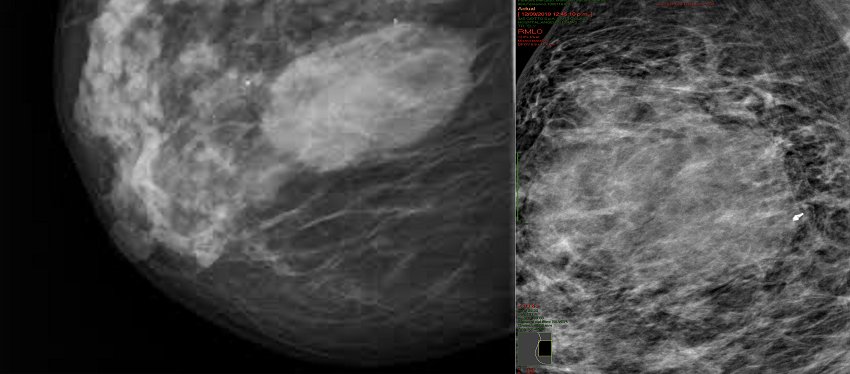

En la mamografía por tomosíntesis (Figura 1) se reportó tejido heterogéneamente denso en ambas glándulas mamarias. En la glándula mamaria derecha, en el cuadrante superior externo, se reportó engrosamiento difuso de la piel, con un patrón denso que sustituía la mayor parte de la glándula mamaria y se extendía de forma irregular, así como un nódulo ovalado, con márgenes indistintos y microlobulados de aproximadamente 1,5 cm en su eje mayor. Contaba con calcificaciones puntiformes, en anillo y distróficas, típicamente benignas, en ambas glándulas mamarias. En las axilas se reportaron ganglios de tamaño y forma adecuada.

El estudio se complementó con ecografía mamaria (Figura 2), la cual reportó tejido mamario fibroglandular y heterogéneo, con distorsión de la arquitectura, con un tumor en glándula mamaria derecha en el radio de la 1, bordes microlobulados y heterogéneos debido a zonas de mayor y menor ecogenicidad en el interior, sin reforzamiento posterior, con vascularidad interna incrementada a la aplicación de Doppler color. Los complejos areola-pezón con ductos de calibre y distribución adecuados. A nivel cutáneo se apreció engrosamiento de la piel. En las axilas se reportaron ganglios de tamaño y forma adecuadas, que conservaban su centro graso.

Una vez integrados los estudios de imagen se otorgó una categoría Breast Imaging Reporting and Data System (BI-RADS) 5, según el sistema del American College of Radiology, por lo que se prosiguió a realizar biopsia con aguja gruesa guiada por ultrasonido para su estudio histopatológico.